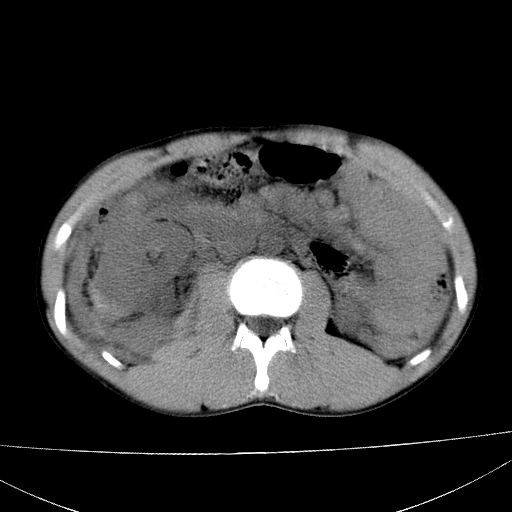

标题: CT15860:男,21岁,腹部外伤2小时伴胸疼。 [打印本页]

标题: CT15860:男,21岁,腹部外伤2小时伴胸疼。

肝肾挫裂伤,右肾周及包膜下血肿,腹腔积液,不排除空腔脏器穿孔,建议行增强检查

肝、右肾包膜下血肿,右侧腰大肌及腹膜后血肿;腹腔少量积血;腹腔疑有少量游离气体伴肠破裂。

1肝挫伤伴腹腔积液。2右肾挫裂伤伴右肾包膜及肾后间隙肿血肿。3右肾脏周围的积气,十二指肠显示结构不清,考虑十二指肠降部破裂可能性大。